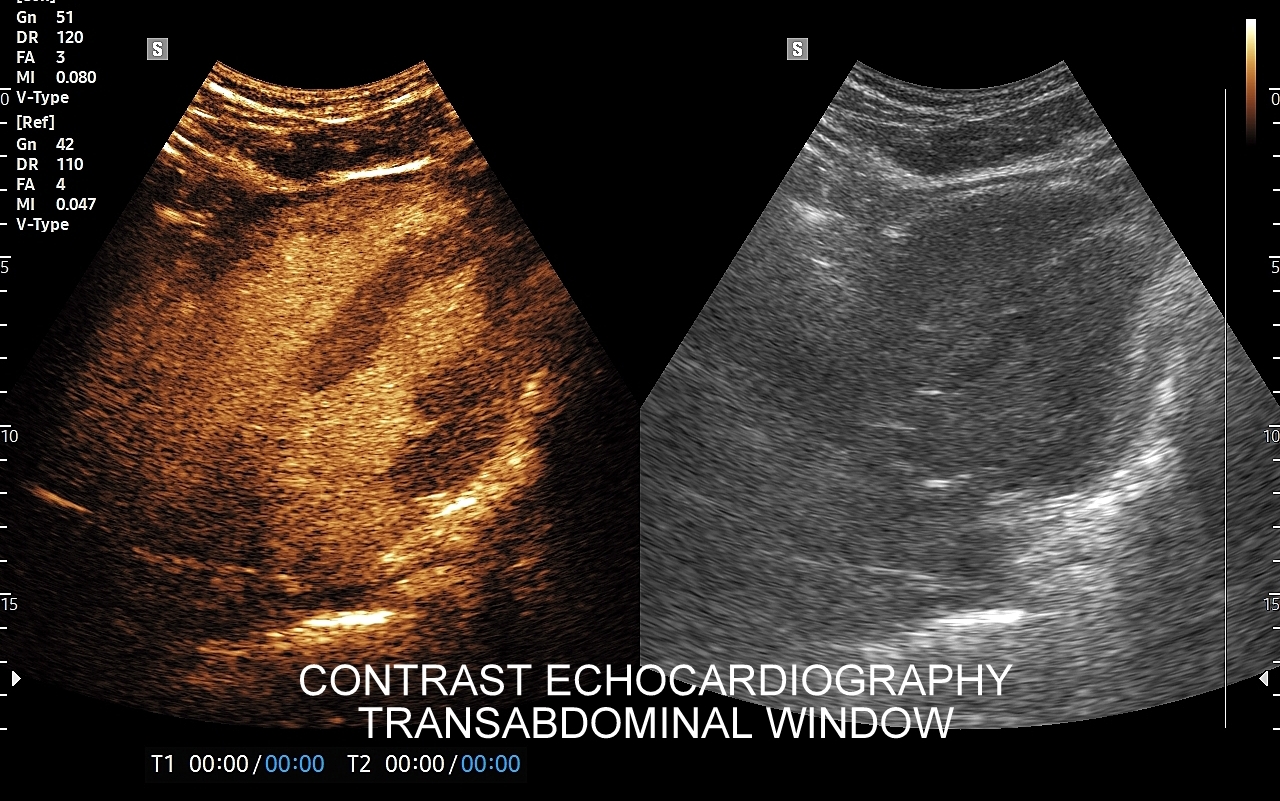

Badanie USG z kontrastem, z języka angielskiego CEUS (contrast enhanced ultrasound), jest badaniem ultrasonograficznym, podczas którego, zwykle dożylnie, podaje się specjalny kontrast w celu uwidocznienia struktur narządowych oraz tkanek, które niewystarczająco wyraźnie są widoczne lub charakteryzowane w klasycznym badaniu USG, a nawet w innych badaniach obrazowych jak tomografia komputerowa (TK) czy rezonans magnetyczny (MRI).

Strukturę kontrastu do USG stanowią mikropęcherzyki o wielkości <10 μm zbudowane z osłonki lipidowej, w której zamknięty jest neutralny gaz heksafluorek siarki (SF6). Mikropęcherzyki po podaniu dożylnym przedostają się mikrokrążenia narządów i są w nich wykrywane za pomocą obrazowania USG specjalnie do tego przystosowanym aparatem. Oprócz dożylnego podawania kontrastu, w przypadku niektórych wskazań, może być on także administrowany dopęcherzowo.

CEUS jest badaniem w czasie rzeczywistym pozostającym pod kontrolą operatora, podczas którego możliwe jest wykonanie próby czynnościowej oraz natychmiastowe powtórzenie całego badania w razie konieczności. Możliwości takich nie dają ani TK ani MRI. Dodatkowo CEUS cechuje się o wiele większą rozdzielczością czasową w porównaniu do wspomnianych metod, co umożliwia uwidocznienie wczesnej fazy tętniczej unaczynienia podejrzanej onkologicznie zmiany ogniskowej w wątrobie i jej lepszą charakterystykę.